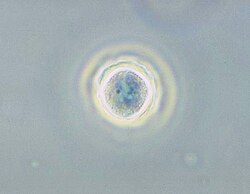

| Phase contrast micrograph of an Acanthamoeba polyphaga cyst. | |